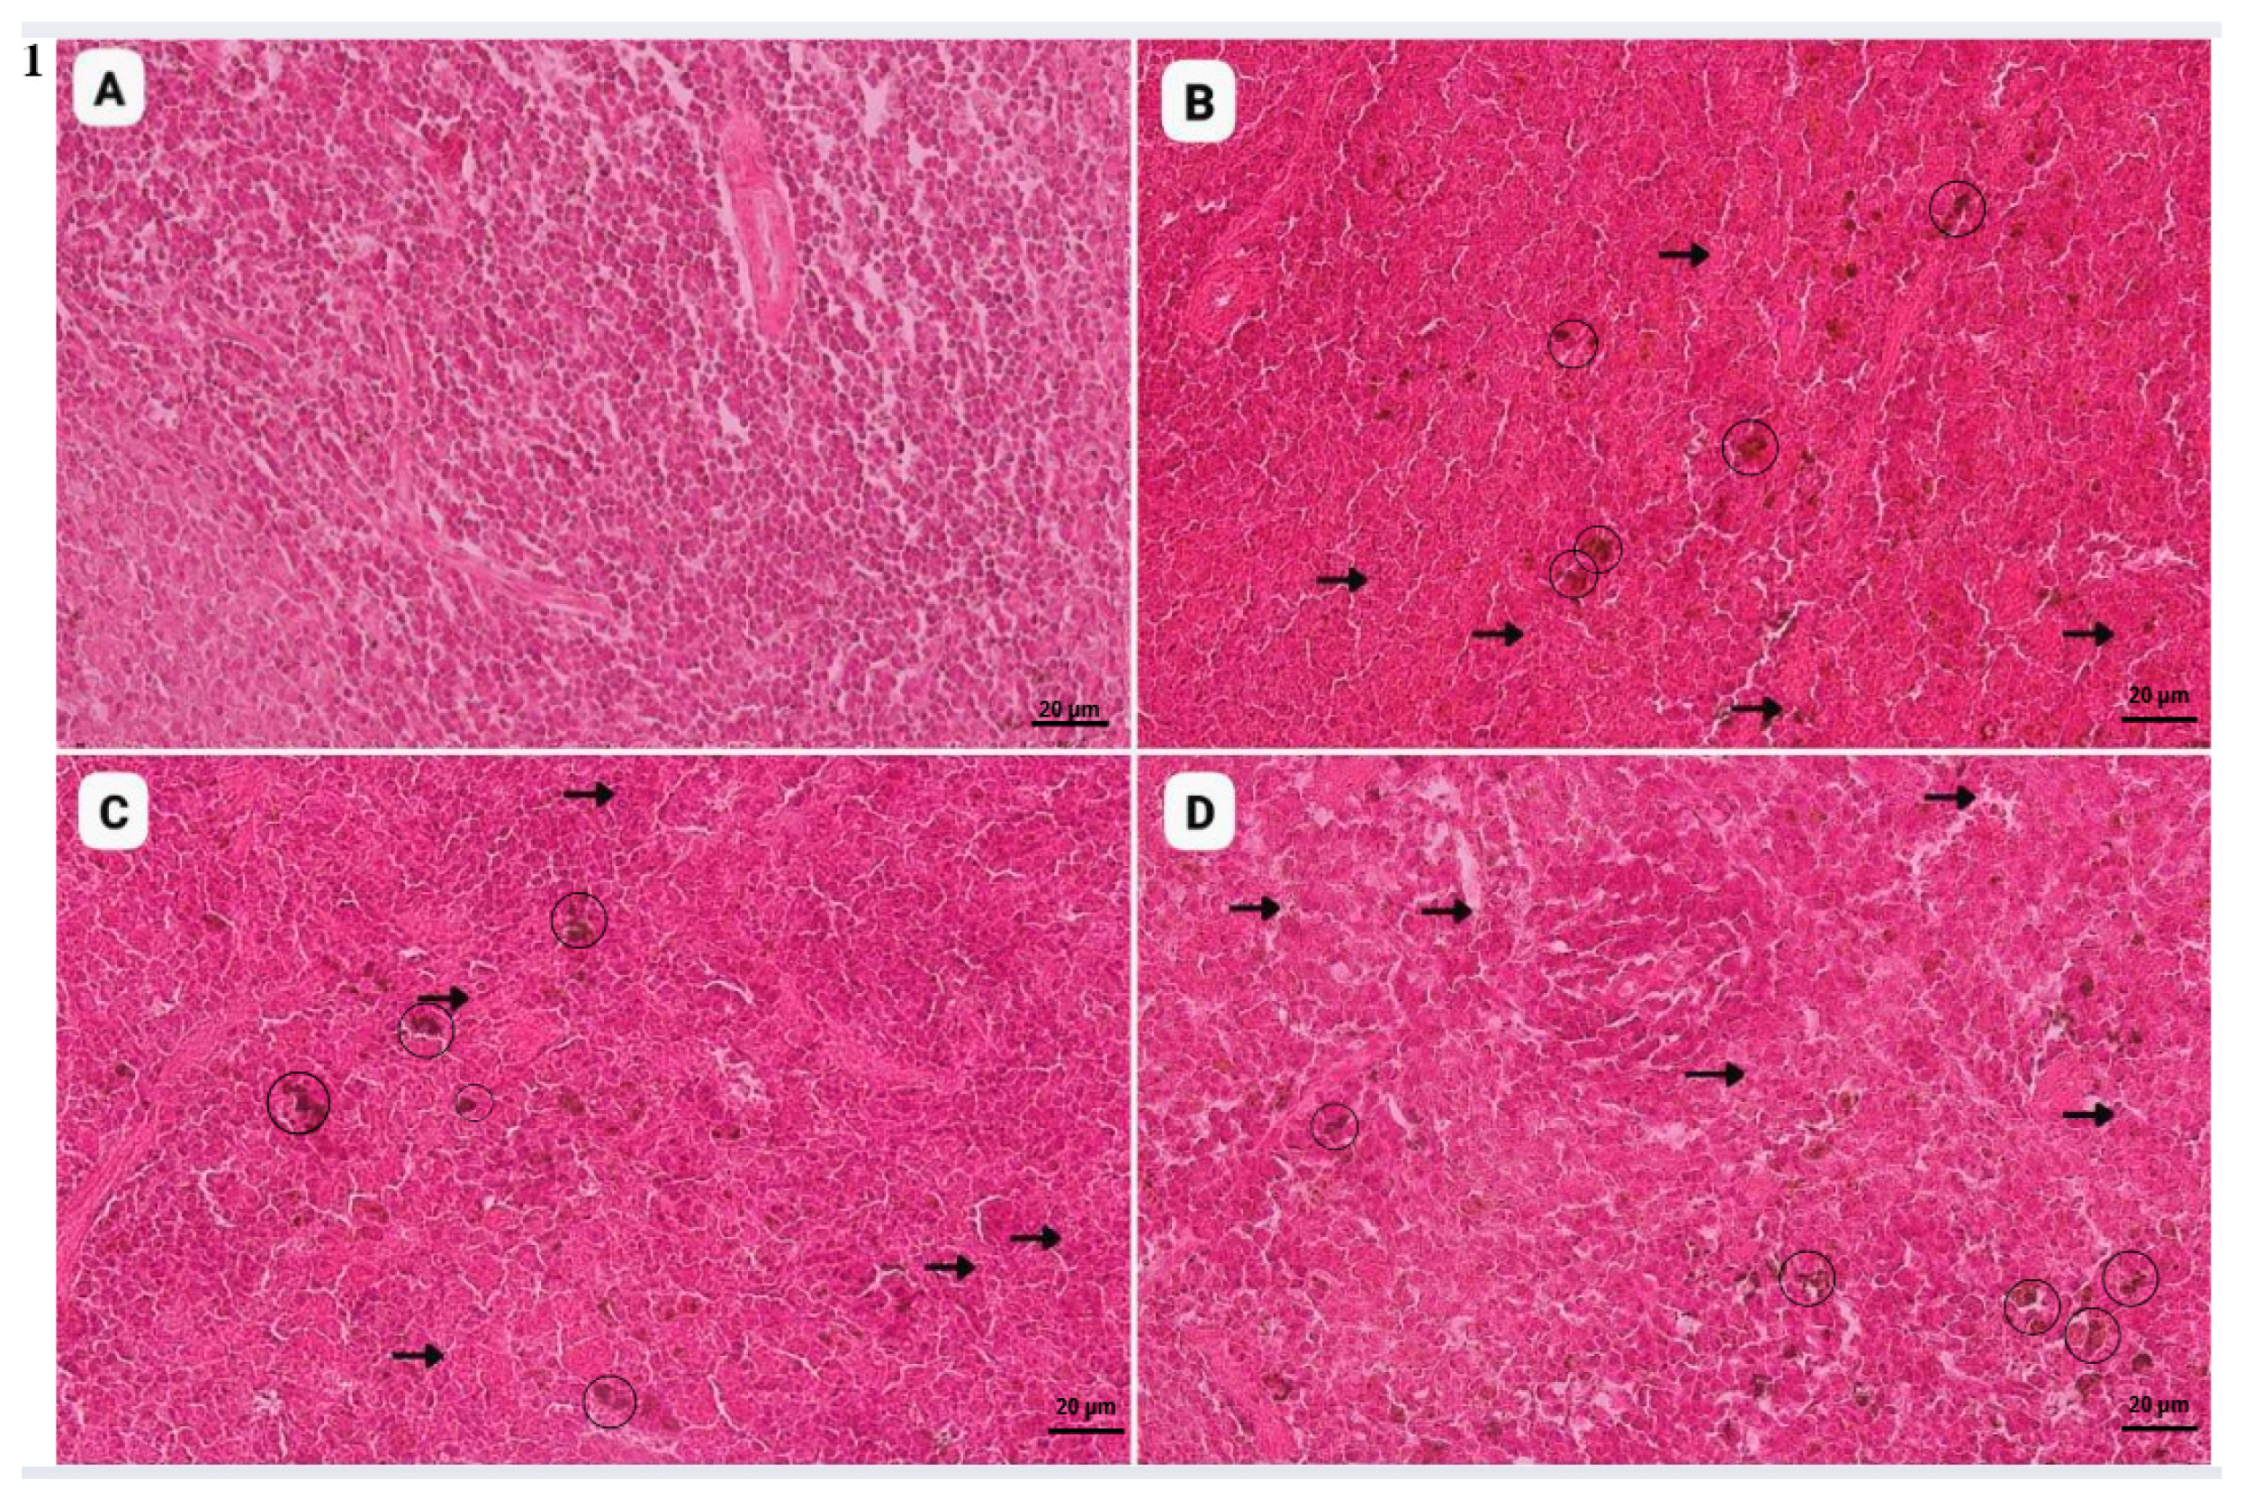

- Cigarette smoke induces lymphoid depletion, leading to white pulp dilation in the spleen.

- Splenic damage includes necrosis and vascular degeneration.

3.2. Histopathological Findings